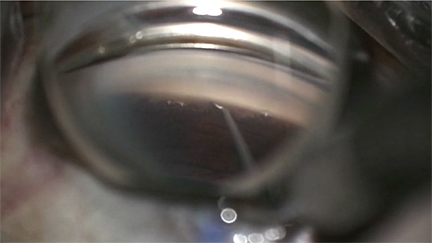

Here, we show a technique to address an overfiltering trabeculectomy flap at the time of surgery. After placement of 3 flap sutures, the flap continues to be leaking at an amount more than desired.

To address this, a compression stitch is fashioned. A 10-0 nylon is passed, distal to proximal, partial thickness through the sclera adjacent to and perpendicular to the edge of the trabeculectomy flap, passed over the flap, and then again passed partial thickness proximal to distal on the other side of the flap. In the same fashion, the suture is then passed back to where it started. Note that the trabeculectomy flap itself is not touched and no additional holes or manipulation is performed on the flap. Care is taken not to puncture the conjunctiva.

The suture is then tied utilizing a slipknot to adjust the tension, with an additional throw to lock the tension as desired. The suture is then buried in a typical fashion. The eye is reinflated with BSS and the trabeculectomy flap now has aqueous flow as desired and is holding pressure. This compression stitch can later be lysed via laser suture lysis in the clinic to adjust outflow. This procedure provides an alternative to the placement of additional flap sutures and managing a persistently leaky flap at the time of trabeculectomy surgery without further flap manipulation.